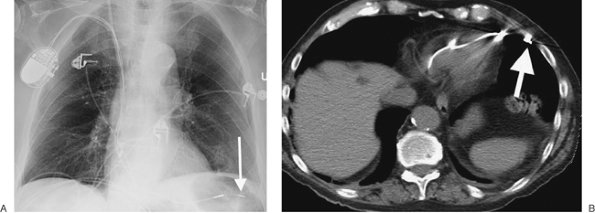

FIGURE 5-12. Pulmonary artery pseudoaneurysm as a complication of pulmonary artery catheter placement. A: AP chest radiograph shows pulmonary edema and the tip of a pulmonary artery catheter projected over an expected left lower lobe segmental pulmonary artery branch (arrow). B: The distal placement of the catheter tip resulted in perforation of a subsegmental pulmonary artery and development of a pulmonary artery pseudoaneurysm, shown as an enhancing mass in the left lower lobe on CT (arrow).